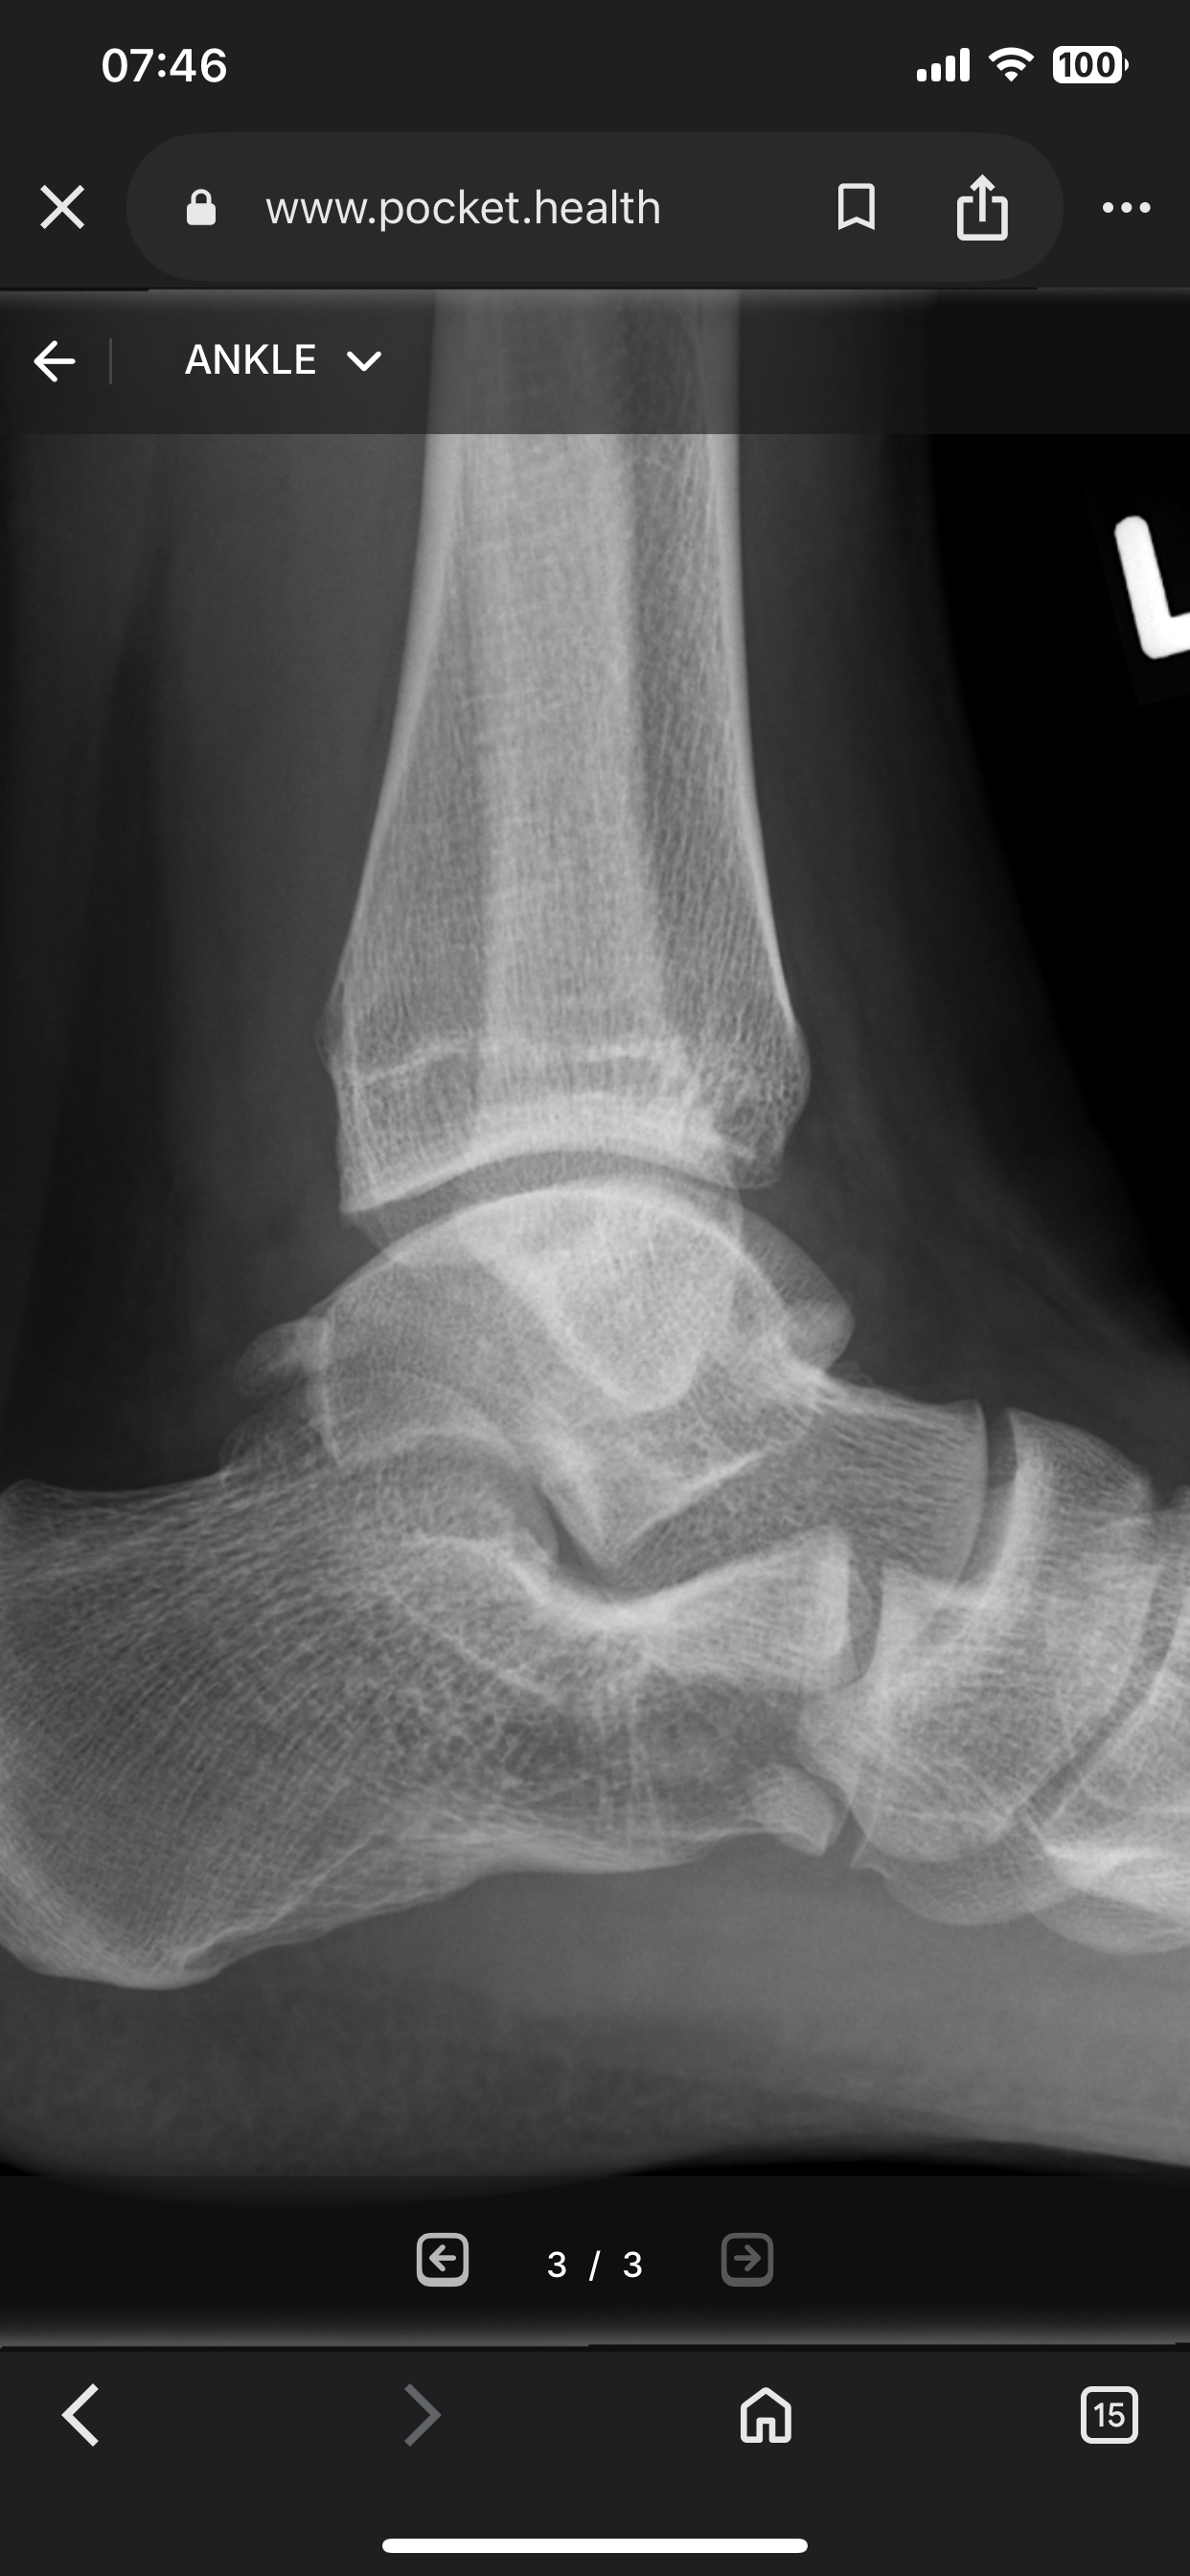

I’m fucking 5”7 and they’re fused fuck my life bro

IMG 4316